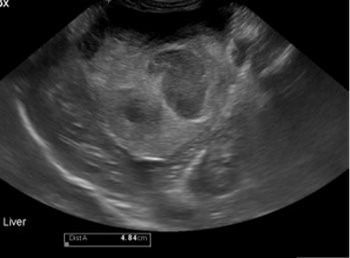

The transcatheter edge-to-edge repair procedure is a minimally invasive treatment for mitral regurgitation.